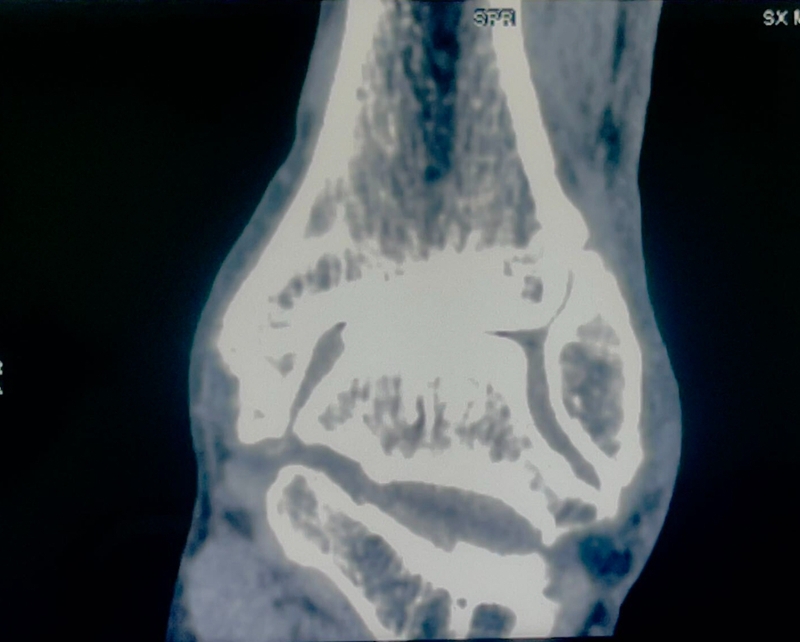

病例报告之二,xx,男,56岁,左踝创伤性关节炎。左踝崴伤6年,疼痛加剧3年。切口显露同前。

手术前资料

手术中资料